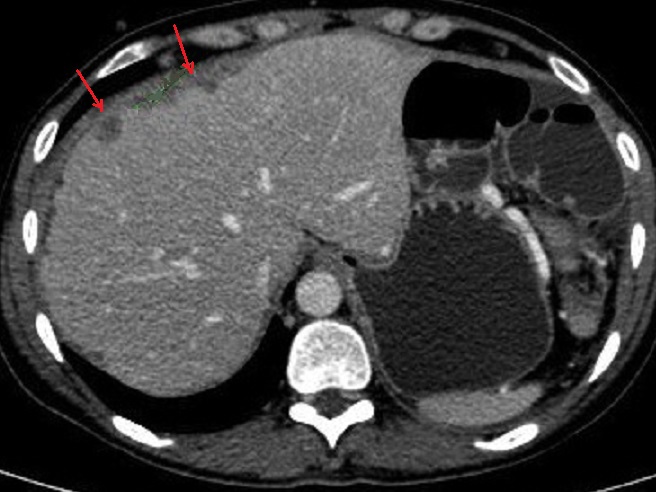

Image

radiologique de dilatation du VBP et des voies

biliaire intrahapatique d'une tumeur de la tete

dupancreas . Coupe TDM axiale . |

Image de distention legere

de la vesicule biliaire ( VB ) et de voie biliaire

principale ( VBP ) . |

Image radiologique d'une

adenocarcinoma de la tete du pancreas ( fleche rouge

)avec signe indirect de dilatation du CPP et image

de pseudo-kyste a hypodense au queue du pancreas (

fleche jaune ) . Coupe TDM plus C+ axiale |